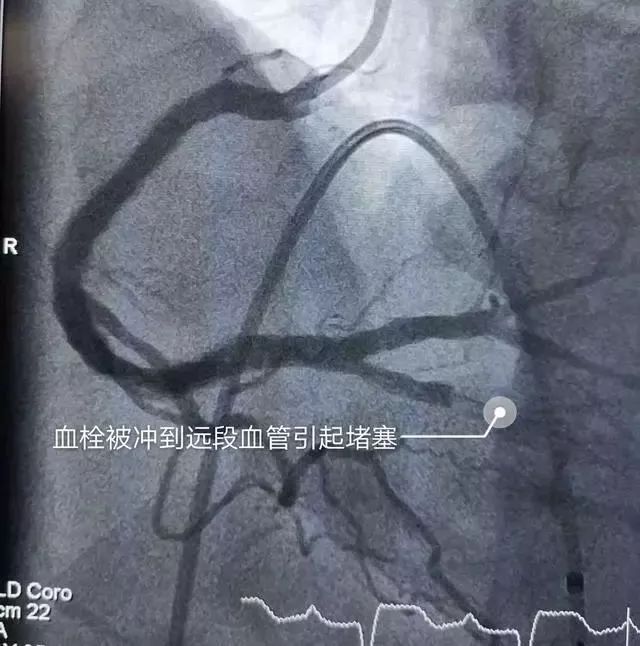

张医生及其团队充分评估病情后,为了让患者最大获益,决定拼一把迎难而上,继续抽吸血栓,经过反复多次尝试,功夫不负有心人,血管内血栓已经抽吸了大部分,时间已经不知不觉过去了一个多小时,就在此时,突然一个血栓脱落,并随血流至远段血管—后降支被堵塞了。

冠脉内马上注射“依替巴肽”(抗血栓药物)并维持静脉泵入后,紧追到后降支继续抽吸血栓,最后经过将近2个小时的不懈努力,终于将肉眼可见血栓全部抽出,并于右冠近段置入支架一枚,复查造影血流非常通畅,完美收工!整个手术过程惊心动魄,这是对团队体力和意志力和双重考验。